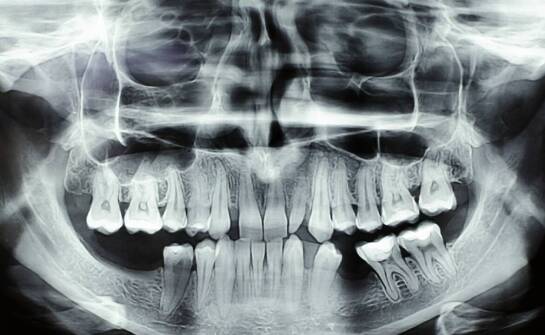

Tomografia komputerowa zębów – jak działa i kiedy może być niezbędna

Tomografia komputerowa zębów (CBCT) to trójwymiarowe badanie, które w kilka–kilkanaście sekund pokazuje zęby, kości szczęk, zatoki i przebieg nerwów z precyzją niedostępną dla tradycyjnego RTG. Jest nieinwazyjna, szybka, a w wielu sytuacjach – jak planowanie implantów, skomplikowane leczenie kanałow